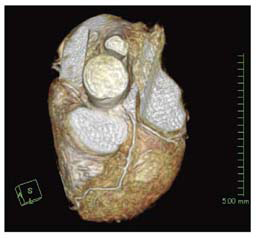

新しい心臓用Volumeアプリケーションである3D Heartでは,心筋信号を抑えるT2-prepパルスが追加されたほか,ペンシルビームを応用した新しい横隔膜同期やスライストラッキング等,さまざまな技術が搭載され,より精度の高い安定した冠動脈描出が可能となっている(図3,4,5)。また,心臓全体をマルチスラブ(5スラブ程度)で撮像することが可能となり,末梢血管の描出能も大きく向上している。

図3 新しい横隔膜同期法やスライストラッキング技術, 図5 図3と同一症例のPWMIP像 |